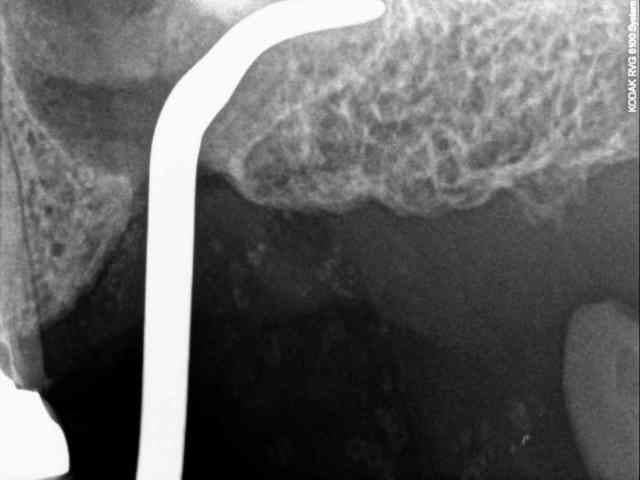

je dois pratiquer un rehaussement de plancher sinusien par volet latéral et je ne sais comment gérer le décollement de la membrane de Schneider au niveau de la communication bucco sinusale

je joins quelques captures pour vous faire une idée

Capt 1957337 h0muvi - Eugenol

Capt 1947248 ubk4pf - Eugenol

Capt 1949039 yc99fq - Eugenol

Capt 1956296 sqhfp8 - Eugenol